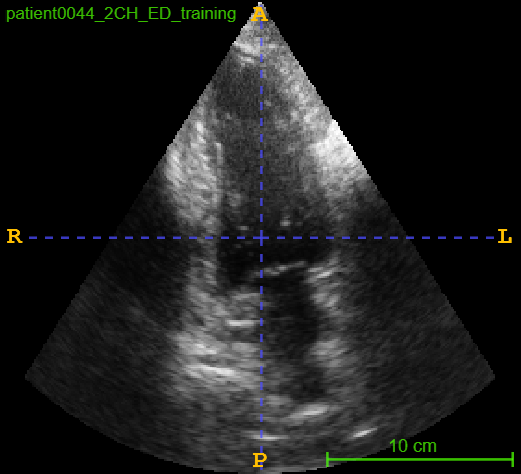

4.3 CAMUS Echocardiogram View Classification

After investigating the issue of synthetic simplicity in the digit classification task, we demonstrate the phenomenon on a representative medical imaging task of cardiac view classification from echocardiographs. We utilized the publicly available echocardiography dataset "Cardiac Acquisitions for Multi-structure Ultrasound Segmentation" (CAMUS) [8] for this experiment. The CAMUS dataset comprises four types of cardiac views from over 500 subjects: two-chamber end-systolic (2CH ES), two-chamber end-diastolic (2CH ED), four-chamber end-systolic (4CH ES), and four-chamber end-diastolic (4CH ED). We focused on the "4CH ED" and "2CH ED" classes in the CAMUS dataset for classification task. Figure 2 shows real and synthetic samples of 4CH ED and 2CH ED echocardiogram views.